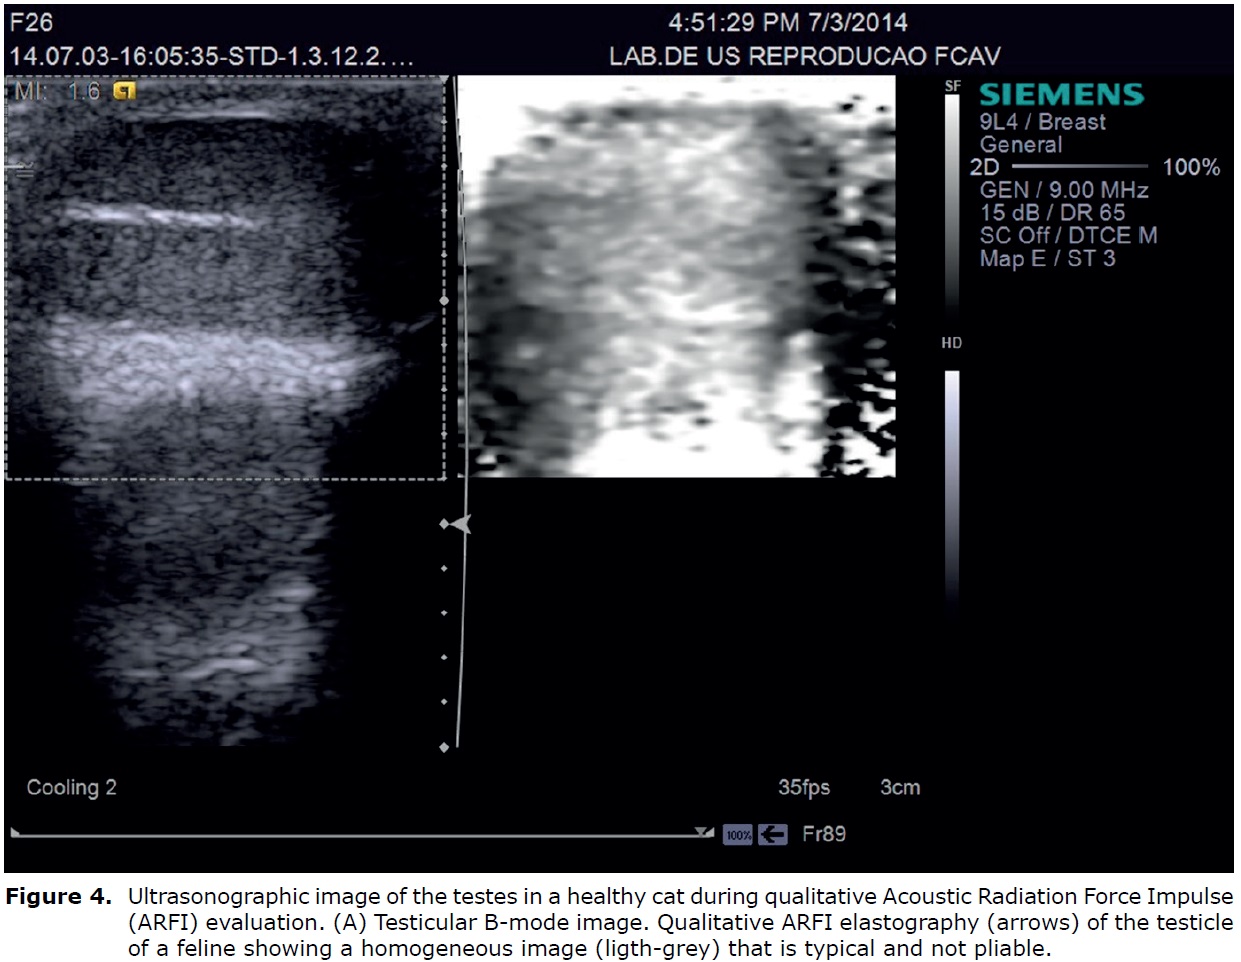

Acoustic radiation force impulse (ARFI) elastography is an ultrasonographic technique that provides quantitative and qualitative measurements of tissue stiffness, with reduced inter-observer variability (8) and this technique involves the generation of shear waves using radiation force impulse or shear force associated with a B-mode image (3).

In qualitative ARFI, short acoustic pulses and high intensities are used to deform the elements of the tissue and create a static map (elastogram) of the relative stiffness of the tissue. Alternatively, the quantitative approach to ARFI utilizes a primary acoustic impulse sent towards a region of interest and promoting the formation of pressure waves capable of deforming the tissues to raise the speed of the wave propagation (shear velocity). The wave velocity and the attenuation of acoustic pressure waves are both related to the rigidity and viscoelasticity of the tissue; the waves have a greater velocity in rigid tissues (40).

This technique was used to evaluate the testes of healthy cats providing novel information on testes elastographic parameters in clinically healthy cats, such as the quantitative values for tissue echogenicity, qualitative and quantitative findings of ARFI elastography. The testes examined by qualitative elastography were free of any malformations and the images appeared as homogeneous dark areas (Figure 4). The mean shear velocity values reported were 1.51 m/s (95% confidence interval: 1.42 and 1.59 m/s) for the right testicle and 1.48 m/s (95% confidence interval: 1.41 and 1.54 m/s) for the left testicle of the felines. There was no significant difference when comparing the right and left testicular structures (44) (Figure 5).